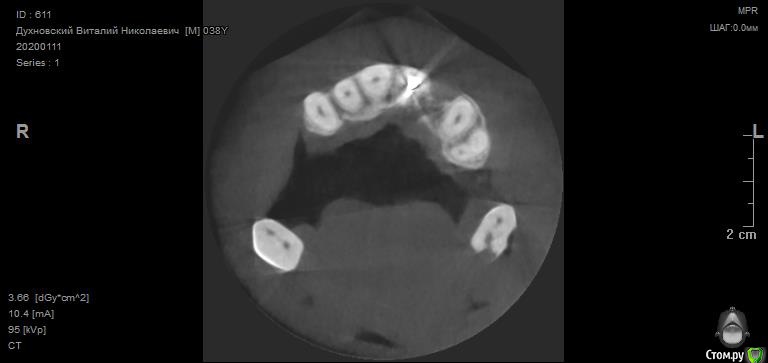

Просьба ко всем не равнодушным! Глянуть КТ верхней челюсти, 27 зуб  и место где удалили 16, может ещё где-то могут быть проблемы.  На фото видно где покраснение на дёснах, в этих местах возникают боли при движении головой. Бывает боль слева если засыпаю на левой стороне. Набуханий или флюсов нигде не видно.Прошу делиться мнениями, для меня это очень - очень важно. Стоматолог визуальных проблем на месте удалённого зуба не видит, всё зажило.

По данным КТ в зоне удалённого зуба 16 ничего особенного, разве что, ретенированный (непрорезавшийся) зуб 18.

Зуб 27 требует внимания, необходим очный осмотр.

Также стоит обратить внимание на зубы 21 и 24